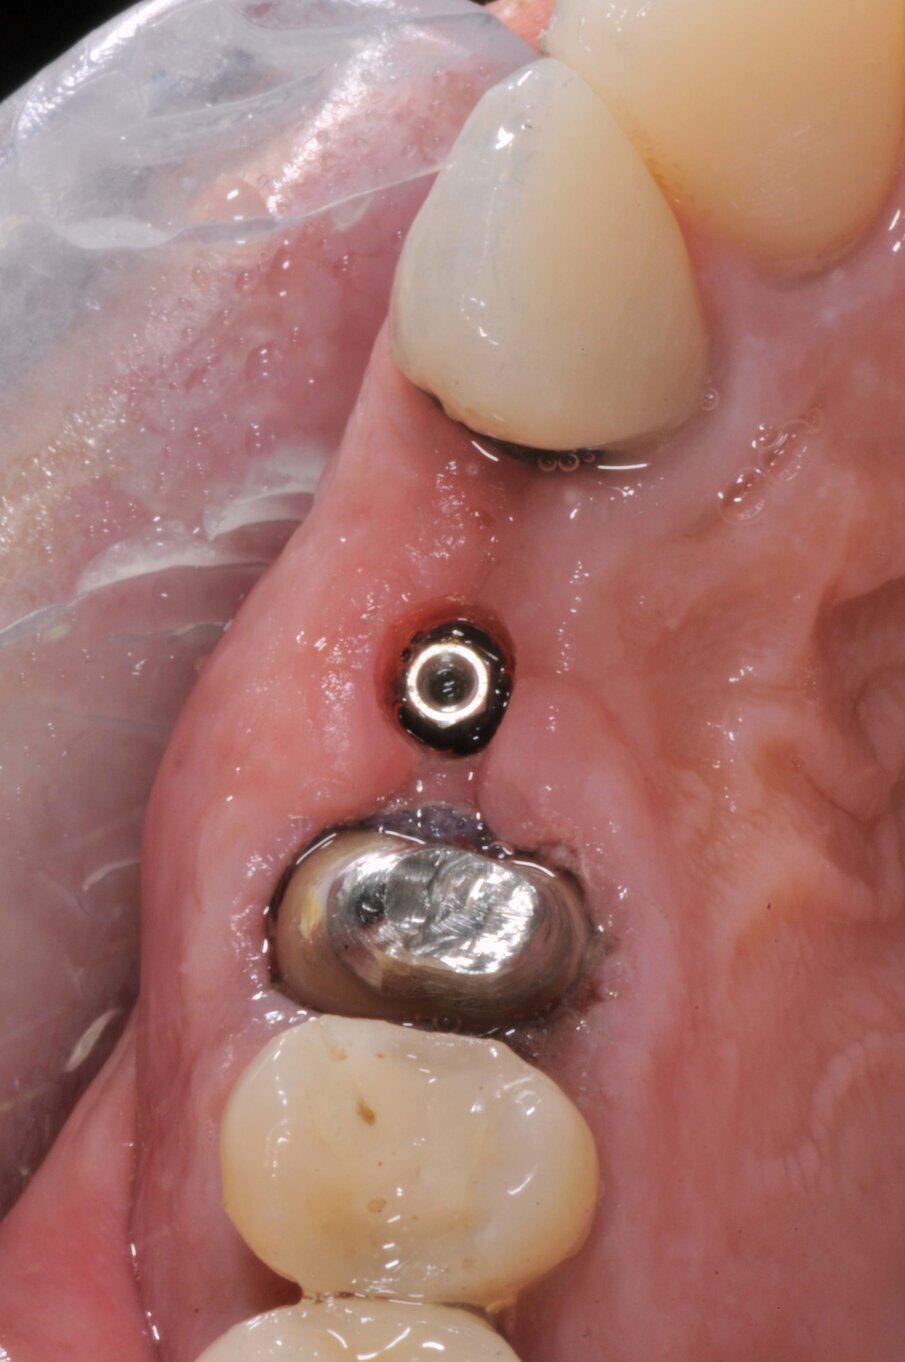

Il dente all’osservazione clinica e radiografica appare devitalizzato e ricostruito per mezzo di una perno moncone fuso e una corona in metallo ceramica collegata ad una corona sul dente 1.4 (Figg. 1, 2). All’esame parodontale si rileva un sondaggio puntiforme in zona palatale che indica la presenza di una frattura radicolare (Fig. 3). La paziente riporta una precedente apicectomia a carico del dente 1.2, come si evince dall’esame come-beam che ne evidenzia gli esiti a carico dell’osso apicale all’elemento 13 (Fig. 4).

Le corone sui denti 1.3 e 1.4 furono rimosse, il dente 1.3 fu estratto e l’alveolo fu riempito con una membrana di PRGF ottenuta tramite centrifugazione del sangue della paziente con il sistema Endoret e un provvisorio fu consegnato sui denti 1.3 e 1.4 (Fig. 5, 6). Dopo otto settimane fu eseguita una nuova cone-beam e la chirurgia fu pianificata (Fig. 7). Si eseguì un lembo a tutto spessore, fu eseguita l’osteotomia e fu inserito un impianto BTI Core 3.5 × 8.5. Un pilastro Unit fu avvitato e un tappo di guarigione fu applicato. L’osso ottenuto dalla fresatura mescolato con una membrana di PRGF fu applicato sul lato palatale per compensare una piccola deiscenza, una seconda membrana fu applicata sopra l’osso circostante e un innesto di tessuto connettivo prelevato dalla tuberosità fu suturato vestibolarmente per ricreare la bozza canina. Punti di sutura staccati furono eseguiti con un filo in PTFE (Figg. 8-11). Dopo quattro mesi il provvisorio fu rimosso e i tessuti apparivano sani e con un buon spessore di tessuto connettivo vestibolare per garantire la stabilità nel tempo del risultato. Fu eseguita un’impronta con la tecnica del cucchiaio aperto e dopo due settimane furono consegnate una corona in zirconio cementata sul dente 14 ed una avvitata sul denta 1.3. Il profilo di emergenza della corona sull’impianto appariva ideale. Purtroppo, a causa della mancanza del picco osseo sul versante distale del dente 1.2, non si ottenne una papilla di altezza adeguata. Ciononostante la paziente si disse soddisfatta del risultato e rifiutò ulteriori terapie per correggere il difetto residuo (Figg. 12-15).